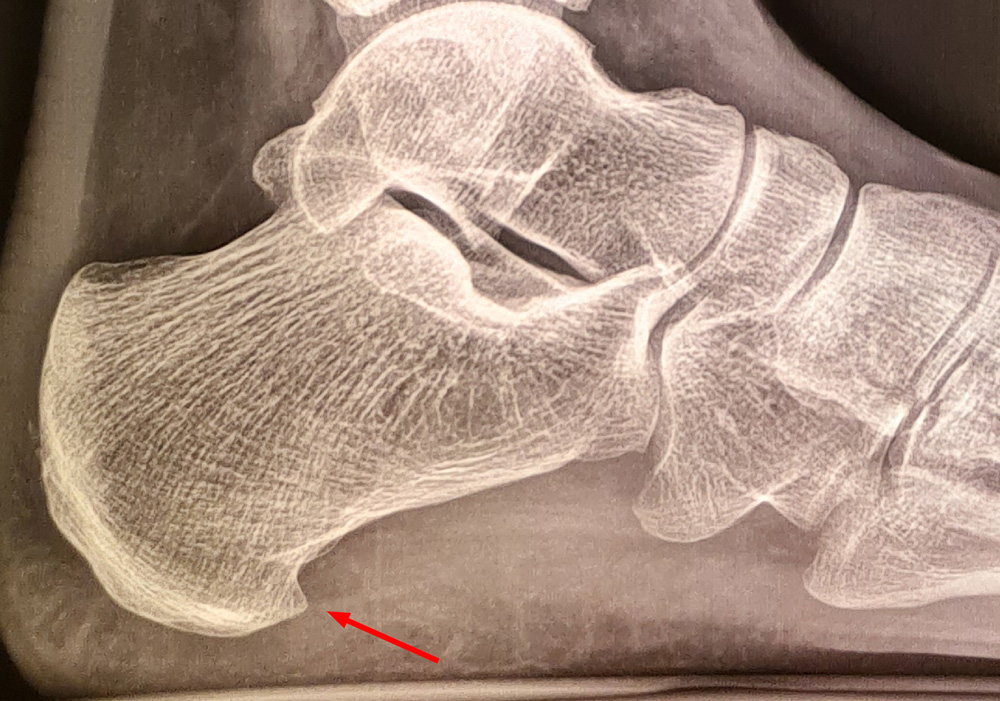

Beispiel 1:

Minimalinvasive Abtragung eines plantaren Fersensporns

Bild 1: ein schmerzhafter plantarer Ferssensporn. Bilder 2 und 3: Durch einen wenige Millimeter großen Hautschnitt wurde mit der Fräse der Fersensporn abgetragen. Zusätzlich wurden die in der Umgebung befindlichen Nervenenden verödet.